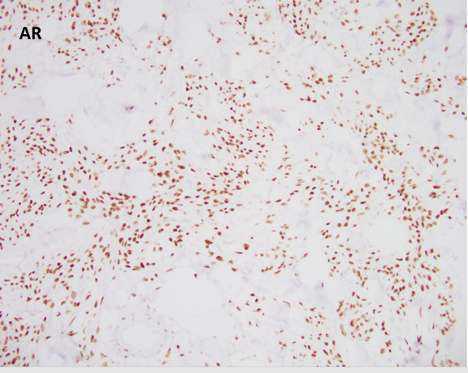

Myofibroblastoma (MFB) is an uncommon myofibroblastic lesion, typically seen in older patients. It occurs in both males and females and usually presents as a slow growing, palpable, painless breast mass. Most lesions are small, 1-4 cm; however, cases of giant myofibroblastomas have been reported. Histologically, the lesion is characterized by a well-circumscribed mass composed of spindle cells intermixed between bundles of hyalanized collagen. Because the neoplasm is myofibroblastic in origin, immunohistochemical markers such as Smooth Muscle Actin (SMA), Muscle Specific Actin (MSA), and Desmin are characteristically positive. Myofibroblastomas are also typically positive for CD34, estrogen receptor (ER), progesterone receptor (PR), and androgen receptor (AR). The cells of interest are negative for cytokeratins. Genetically, the entity is characterized by loss of 13q14 and 16q. As a result, there is inactivation of genes RB1 and FOXO1, and as such, loss of Rb expression via immunohistochemistry. Treatment typically consists of surgical excision with no additional therapy required.

All of the other answer choices may be considered in the differential diagnosis, especially on biopsy. Metaplastic carcinomas can be comprised of spindle cells with or without an epithelioid component. However, the stromal collagen is typically not present and the cytology is much more pleomorphic with frequent mitosis and an infiltrative growth pattern. Additionally, metaplastic carcinomas will be positive for cytokeratin immunohistochemistry and negative for hormone receptors ER/PR/AR, CD34, and desmin/myofibroblastic markers. Phyllodes tumors are also neoplasms of stromal differentiation. Phyllodes tumors, however, show both the presence of spindle cells and benign epithelium, typically creating a “leaf-like” architecture. IHC is positive for CD34 but Rb staining is retained. Pseudoangiomatous stromal hyperplasia (PASH) usually doesn’t form a mass; however, it is a myofibroblastic lesion with a similar staining pattern, SMA, desmin, ER, and PR positive. Histologically PASH has a dense collagenous stroma with prominent slit-like spaces. Additionally, the characteristic genetic alterations found in MFB are not present.